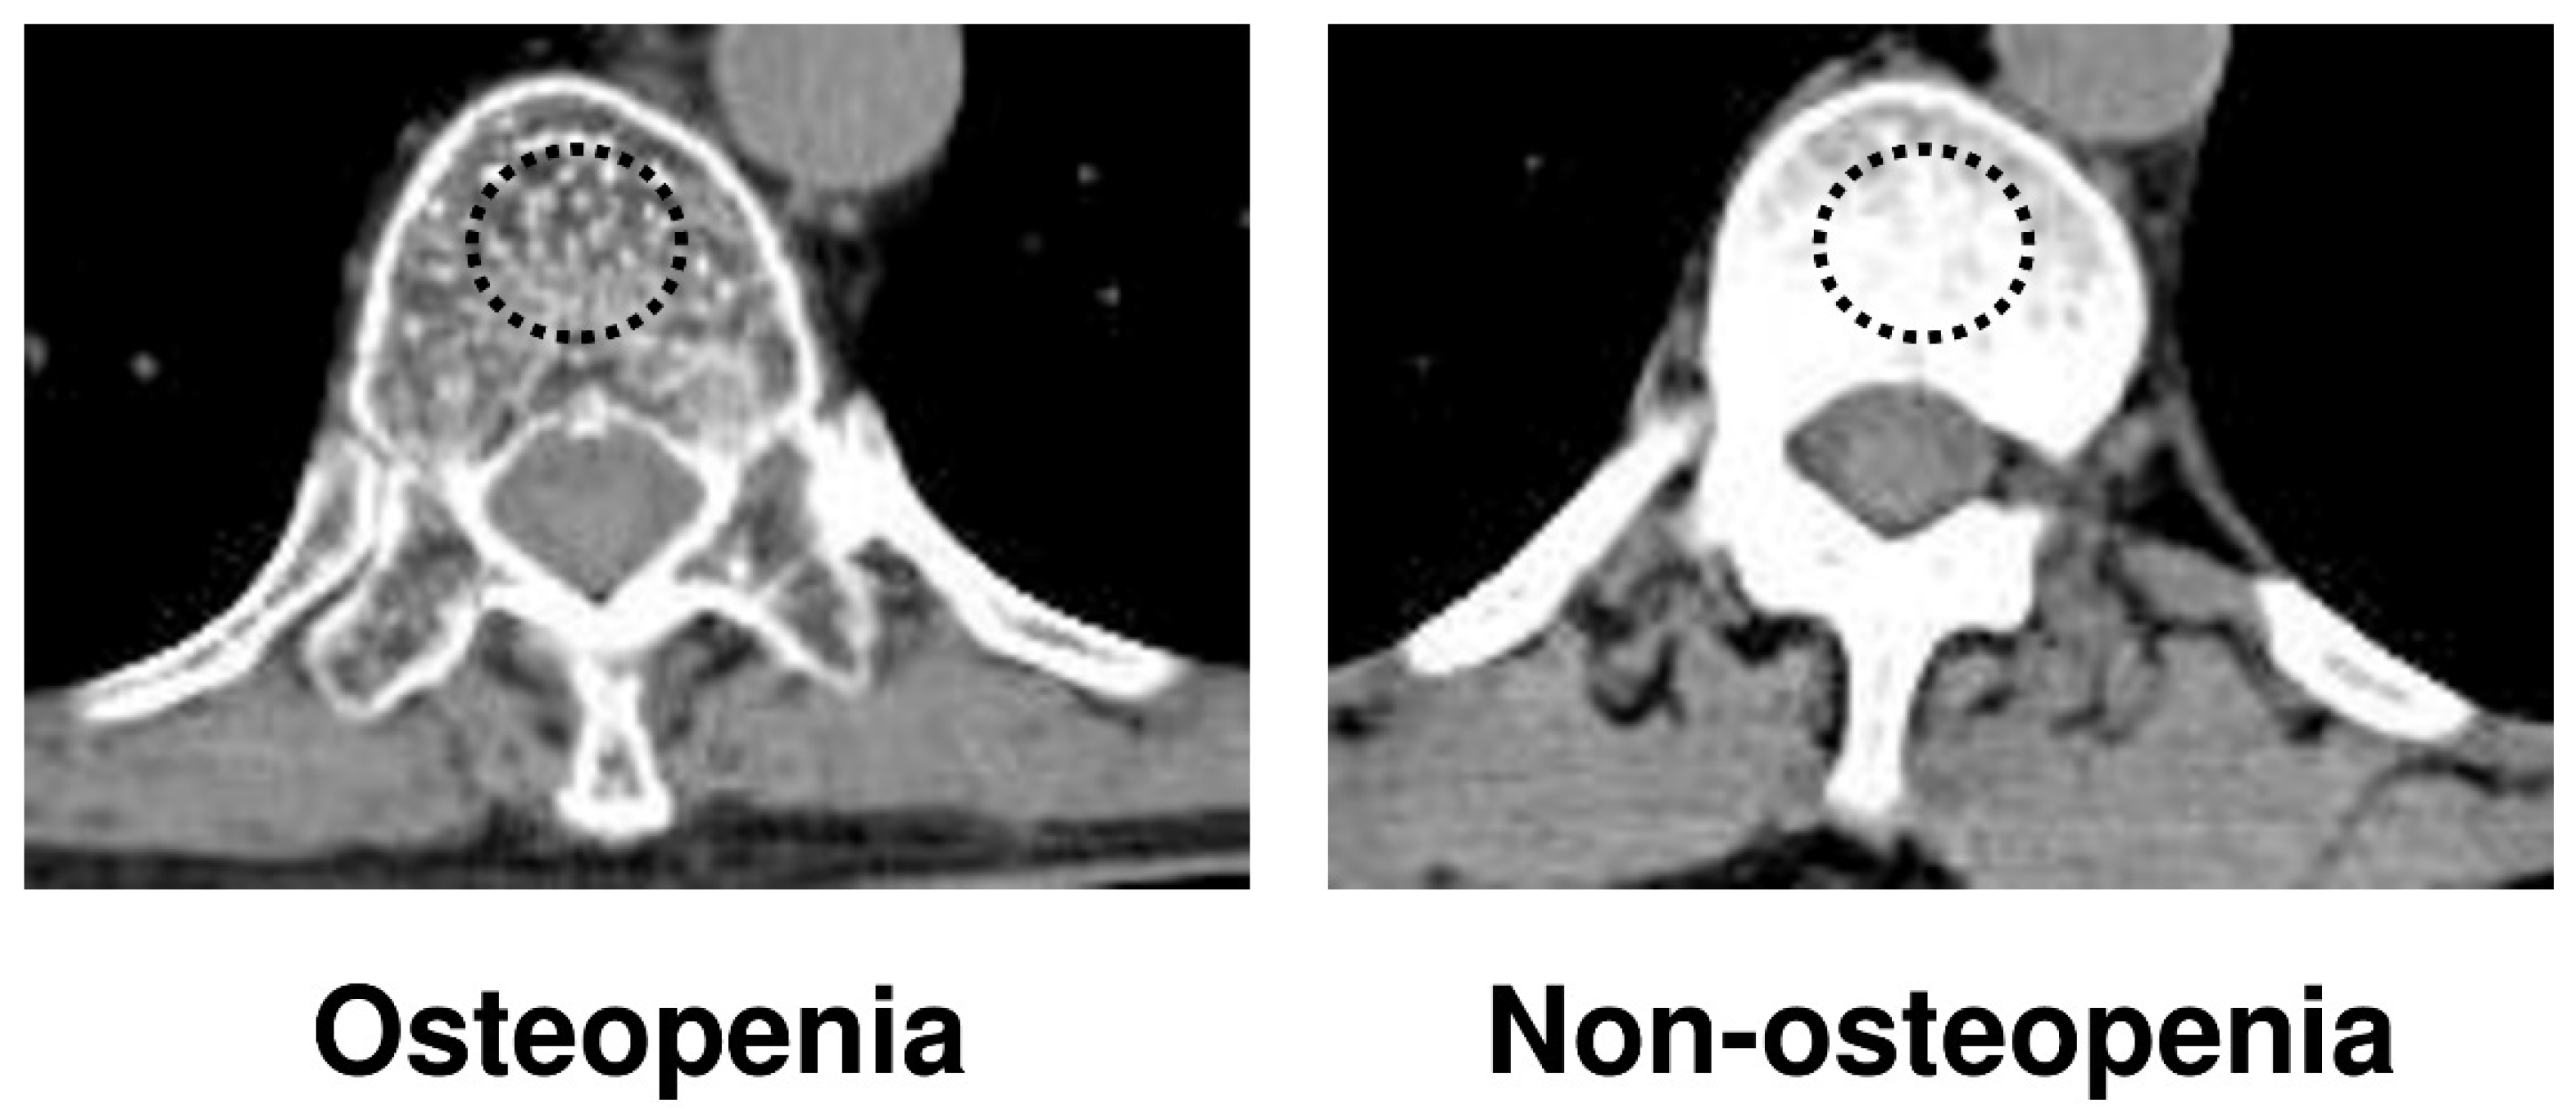

2.2. Detection of Osteopenia